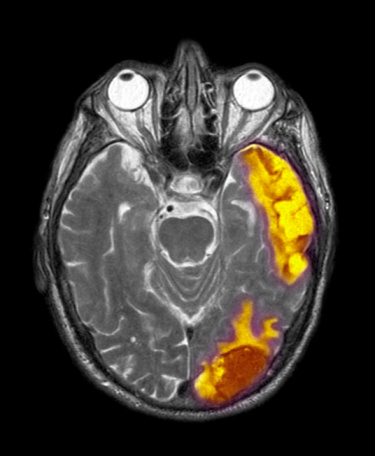

腦腫瘤分為原發性和繼發性兩大類,高危年齡貫穿20―50歲,因此即使年紀輕輕,也很有可能中招。所幸,還是有一些信號能提醒人們盡早發現它。